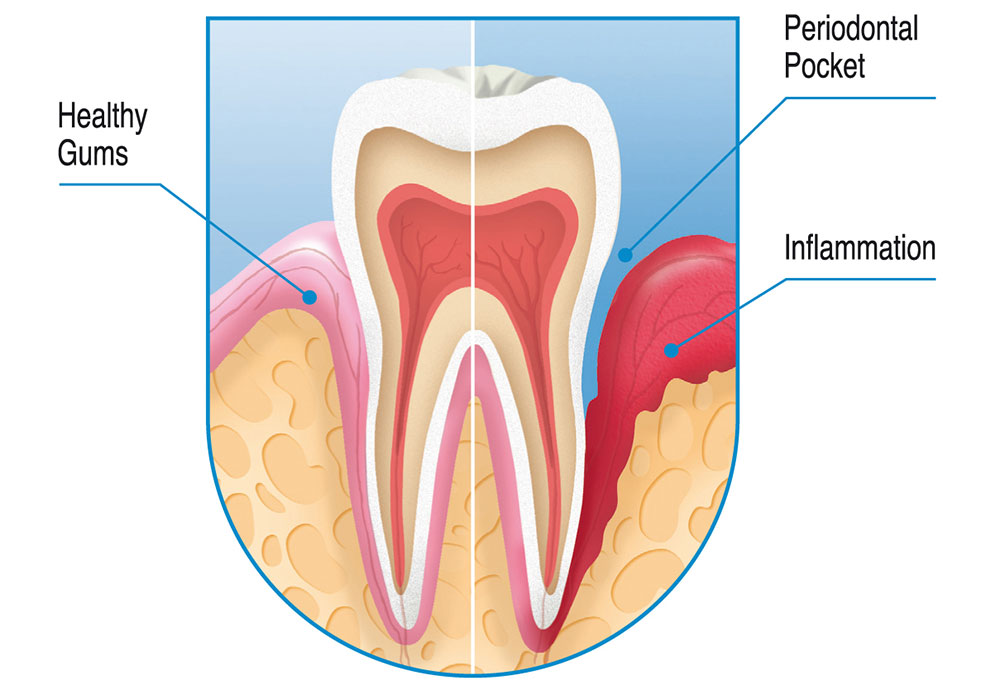

عدم رعایت بهداشت دهان و دندان از علل اصلی خونریزی لثه محسوب میشود. ورم لثه و التهاب لثه باعث میشوند لثه حساستر شده و بیشتر مستعد خونریزی شود. بیشتر افراد زمانی که مدت زیادی پلاک دندانی روی خط لثه باقی میماند، دچار ورم لثه میشوند.

طبق گفته انجمن دندانپزشکی آمریکا (ADA)، بیماری پیرادندانی یا التهاب لثه زمانی اتفاق میافتد که ورم لثه پیشرفت کند. بیماری پیرادندانی، عفونت لثه، استخوان فک و بافتهای حمایتکنندهای است که به دندانها و لثه متصل هستند. ورم لثه ممکن است باعث شل شدن یا افتادن دندان شود.